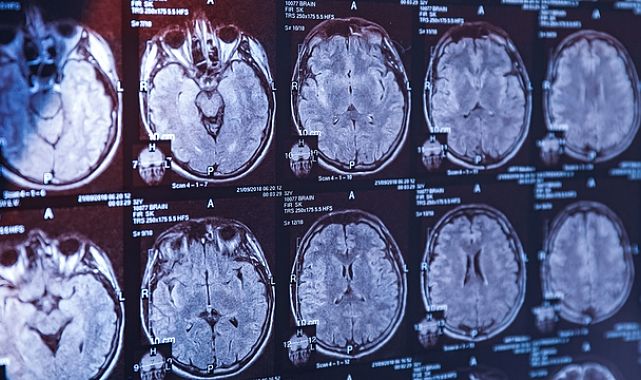

Prof. Dr. Hanoğlu, Alzheimer’ın uzun yıllar boyunca klinik belirtilerle tanılandığını, ancak son dönemde biyobelirteçlerin ön plana çıktığını söyledi. Daha önce belden sıvı alma (lomber ponksiyon) yöntemiyle yapılan testlerin yerini artık basit kan testleri alıyor.

Son iki yılda Alzheimer tedavisinde de gelişmeler yaşandı. Monoklonal antikor tedavilerinin kullanımı yaygınlaşırken, beyindeki amiloid plakları hedef alan bu tedavilerin hastalığın seyrini yavaşlattığı gösterildi.